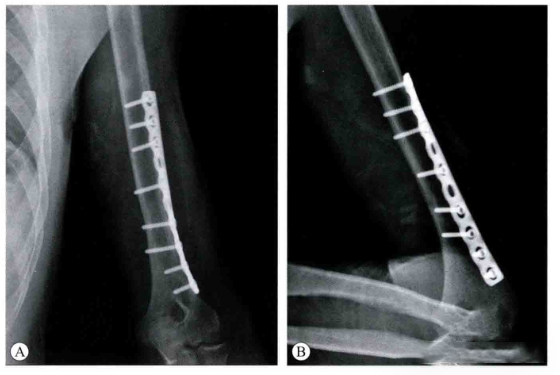

Магический эффект проксимальной пластины плечевой кости при малоинвазивном лечении дистальных перело

Оптимальное лечение переломов дистального отдела плечевой кости технически сложно и противоречиво. Одним из методов ···

узнать больше

2024-07-10

Classic Reappearance - Подробное объяснение этапов и методов минимально инвазивного пластинчатого ле

В последние годы малоинвазивная хирургия становится все более популярной. Переломы проксимального отдела плечевой ко···